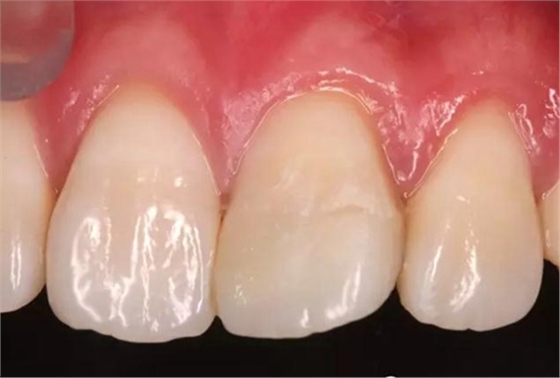

術(shù)后即刻口內(nèi)照

1個(gè)月后患者復(fù)診

口內(nèi)照顯示口腔衛(wèi)生狀況不佳,21牙面呈亞光狀態(tài),齦緣輕度紅腫。

給予健康教育,囑保持口腔衛(wèi)生。再次拋光。

患者1個(gè)半月后復(fù)診,口腔衛(wèi)生狀況保持良好,牙齦健康,折斷線不可見。